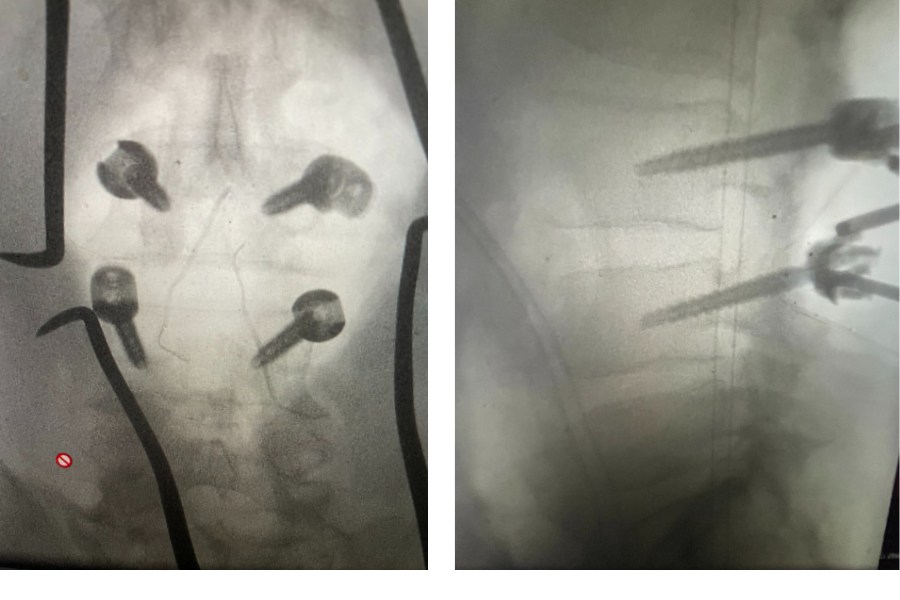

Figure 2. Axial T2-weighted MRI demonstrating severe concentric stenosis at L3-4 due to severely enlarged facet joints and ligamentous hypertrophy

MRI demonstrated severe L3-4 stenosis with a grade 1 spondylolisthesis. He also had L2-3 stenosis. (Fig 1). On axial MRI (Fig 2) he had severe concentric stenosis at L3-4, but on careful examination it appeared that the right side had particular distortion of the anterior aspect of the thecal sac, perhaps secondary to a facet cyst. It seemed more likely coming off the facet joint and not a disc herniation. Although the right side was worse, most of his symptoms were on the left. Why does that happen? I don’t have a great explanation. Clearly the left side is also compressed but sometimes the body just chooses the side to be affected symptomatically when both sides are involved. This is true for compression of the spinal cord for instance in the cervical spine. What is not right, however, is that if a patient has a lateralized disc herniation and the opposite side is symptomatic and without compression, then one should not offer surgical treatment unless that disc is causing severe compression on one side with just less compression on the ipsilateral symptomatic side. Then one can argue that the pathology is having an effect on the opposite side if there is some degree of bilateral compression even if the ipsilateral symptomatic side is less compressed.